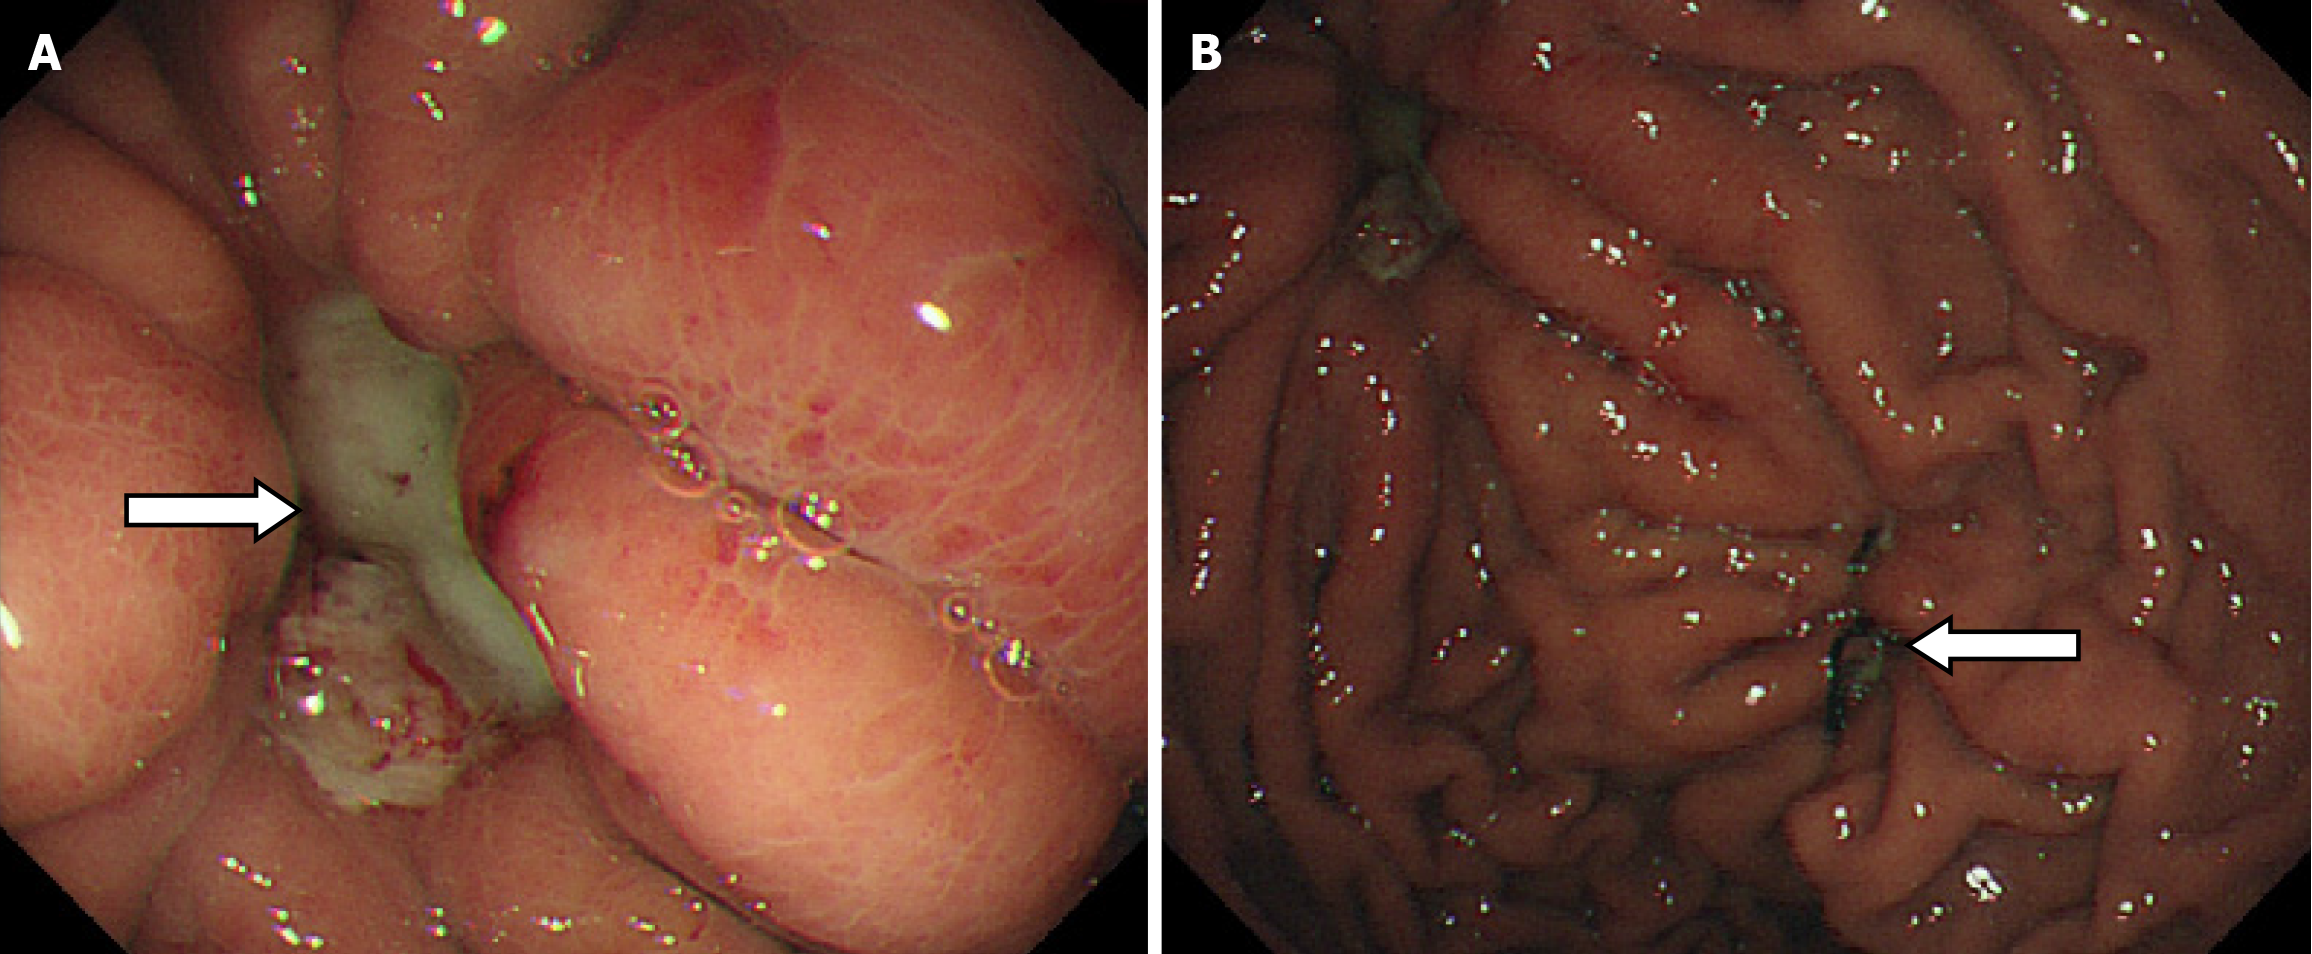

During the postoperative fasting period, we consulted with a nutritionist again. The energy and nitrogen sources were supplied according to the patient's disease status until he returned to a roughly normal diet and then changed to oral enteral nutrition. Drainage tubes of smaller diameter were placed successively and then removed. Reexamination by abdominal CT confirmed that the thoracoabdominal wall swelling had improved (Figure 5), gastric endoscopy verified gastric ulcer improvement and the gastric fistula was not observed at this time (Figure 6). The patient’s clinical symptoms, especially pain, were alleviated. Pathological examination of the sinus showed fibrous and inflammatory granulation tissue with a giant cell reaction. His condition improved and he was again discharged on June 17, 2020.

Therefore, on July 27, 2020, surgery was conducted. Intraoperative exploration found that the abdominal omentums and other organs were adhered to the thoracoabdominal wall as well as each other, the greater curvature of the gastric body was especially seriously adhered to the thoracoabdominal wall. A full-thickness defect of the gastric wall of approximately 2 cm in diameter was observed on the greater curvature of the gastric body. On further examination, the defect was confirmed to correspond with the external ostium on the left upper abdominal wall. Thus, we performed a partial gastrectomy, and the damaged peripheral hard gastric wall tissue was removed, the gastric wall was then sutured with full thickness suturing to close the defect and the muscle layer was embedded. The sinus tissue was then peeled off layer by layer with an electric knife, and the internal ostium of the thoracoabdominal sinus was scratched with a scraping spoon. During the operation, the thoracic surgeon was consulted and decided to postpone the rib related surgery. As expected, after approximately 7 days of fasting and intravenous nutrition, the patient resumed eating and recovered well postoperatively. On August 26, 2020, thoracic surgeons performed sinus resection in the chest wall and resection of the damaged ribs.

Although the patient was discharged with mild pain on September 14, 2020, we were confident that he would have a complete recovery and it was proved by reexamination 3 months later (Figure 7). The patient was then followed up for more than 4 years without recurrence. Time-line about diagnosis and treatment of the patient was shown on Figure 8.